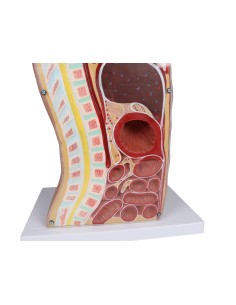

Dal cranio in 22 parti con incastri magnetici ai modelli di colonna vertebrale, da quelli di articolazioni a quelli di cuore, ogni pezzo della nostra collezione è progettato per un’immersione totale nello studio dell’anatomia umana. I nostri modelli, realizzati tramite scansioni di ossa vere, garantiscono un’esperienza tattile autentica e una fedeltà di peso quasi identica agli originali.

Essenziali per studenti e professionisti, i nostri modelli anatomici sono strumenti didattici che permettono di osservare le strutture anatomiche con precisione, eliminando la necessità di dissezioni o studi invasivi. Sono inoltre utili per spiegare ai pazienti le patologie, rendendo la comunicazione più efficace e risparmiando tempo prezioso.